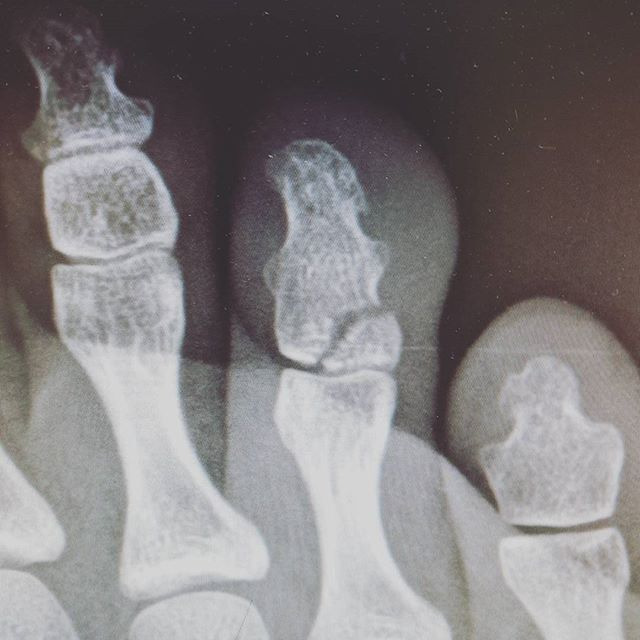

발가락 골절 완치기간 (엄지발가락, 새끼발가락)

발가락 골절은 위치에 따라 회복 과정과 치료 강도가 달라집니다. 발가락은 체중을 지탱하고 보행 시 반복적인 압력을 받기 때문에, 같은 골절이라도 손가락보다 회복이 느리게 진행되는 경향이 있습니다. 특히 엄지발가락은 보행 시 추진력을 담당하는 핵심 구조로, 단순 골절과 복합 골절의 구분이 중요합니다.

발가락 골절의 일반적인 완치기간은 다음과 같은 범위로 정리할 수 있습니다. 단, 이는 평균적인 경과이며 개인의 연령, 기저질환, 생활 패턴에 따라 차이가 발생할 수 있습니다.

- 새끼발가락 및 2-5번째 발가락 단순 골절: 약 4-6주

- 엄지발가락 단순 골절: 약 6-8주

- 전위(뼈가 어긋난 상태)를 동반한 골절 또는 관절 침범 골절: 8주 이상

- 반복 외상 또는 보행 부담이 지속된 경우: 10주 이상 소요 가능